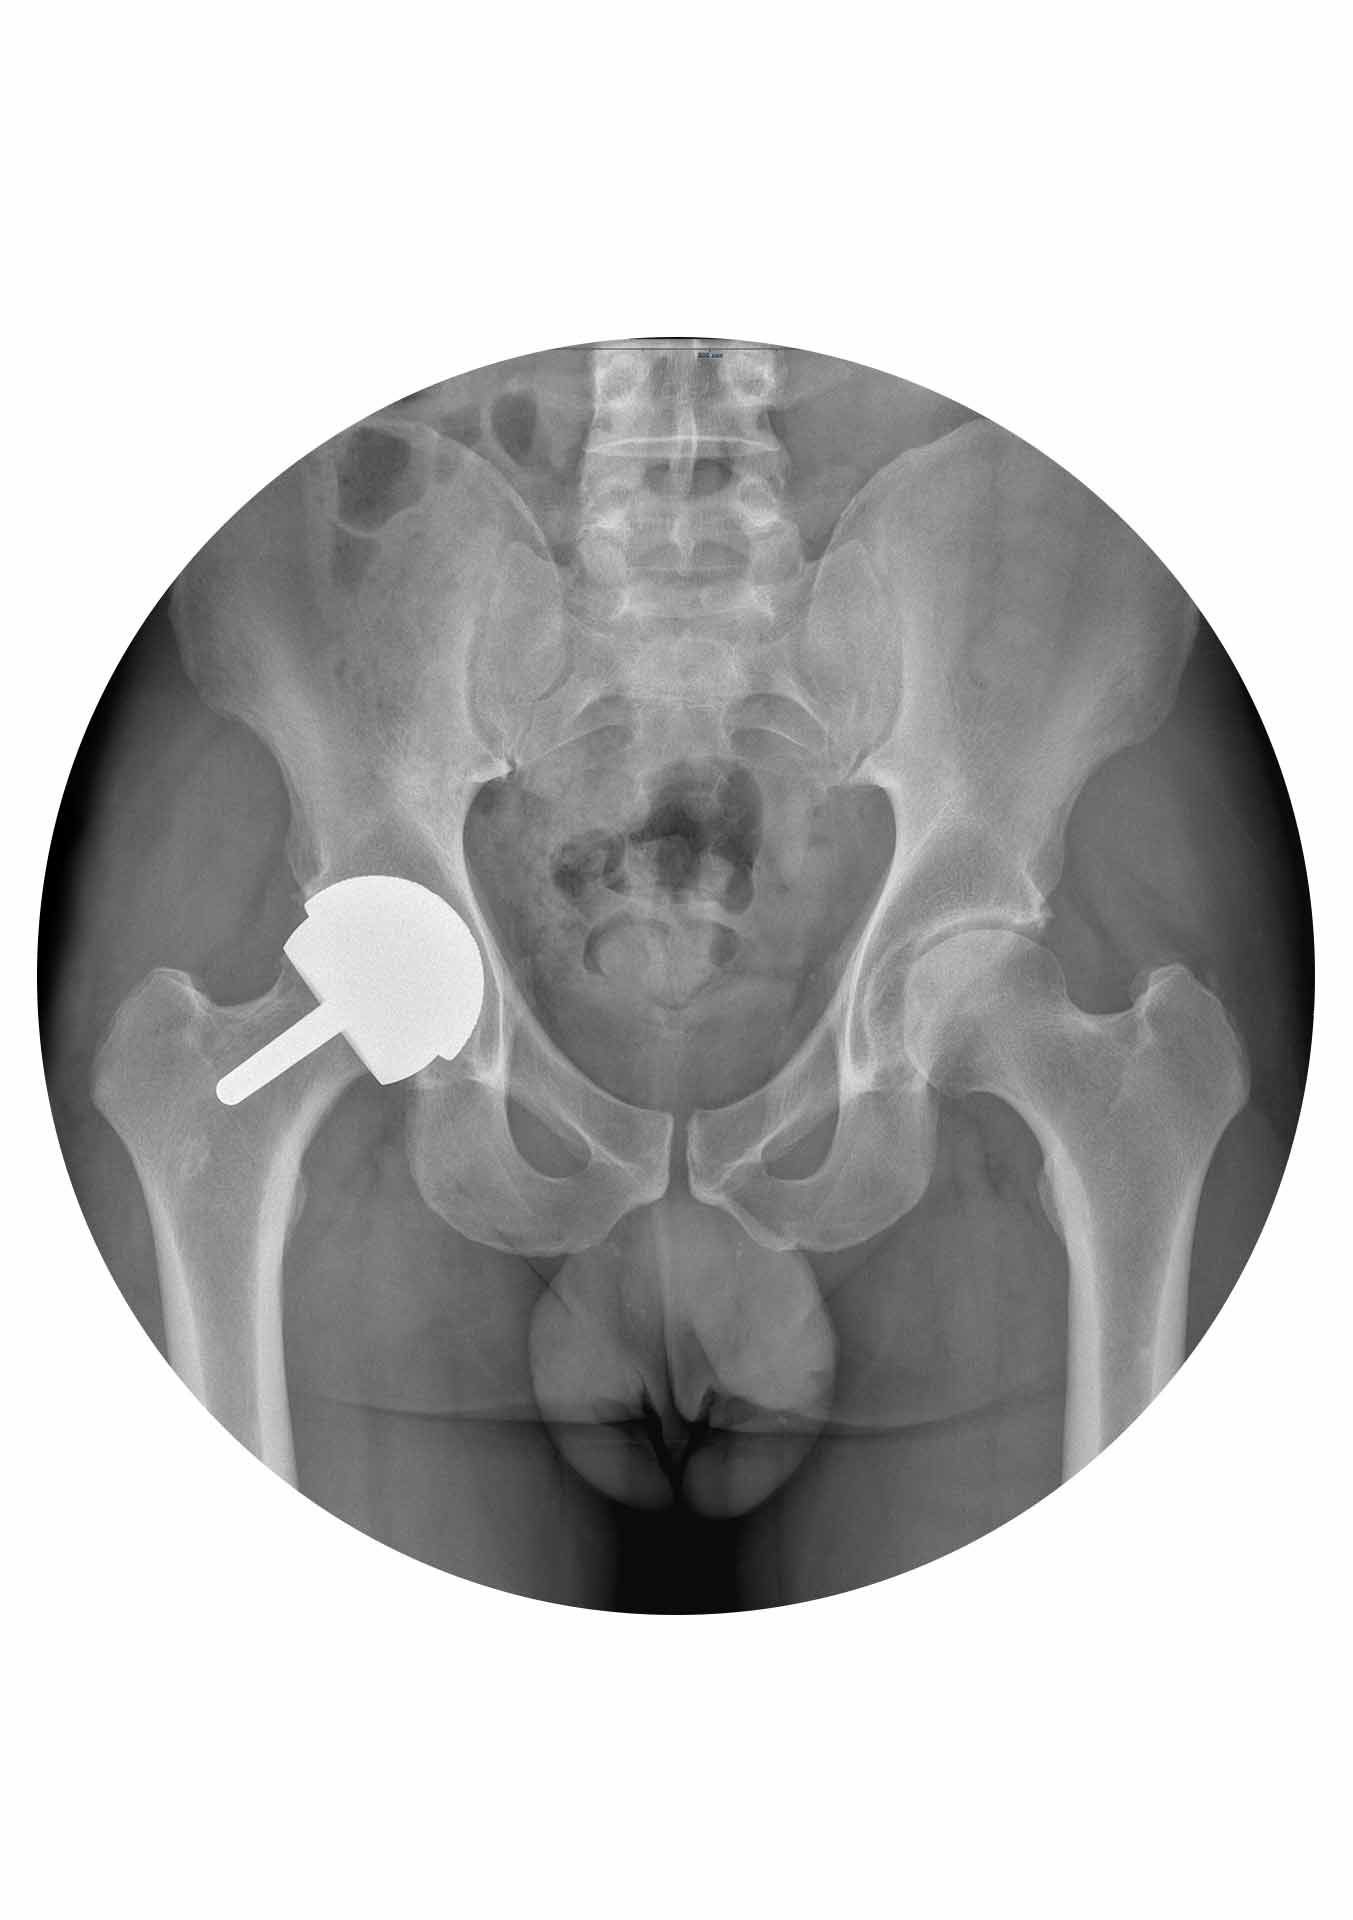

A Birmingham Hip Resurfacing (BHR) desenvolvida pelo cirurgião britânico Sir Derek McMinn tem mais de 20 anos de utilização com provas dadas em várias publicações e registos nacionais e internacionais. Tecnicamente a cirurgia é realizada por uma abordagem lateral (Hardinge – corte na face lateral da anca de cerca de 12 a 15cm) e é necessário deslocar (luxar cirurgicamente) a articulação para se puder “raspar” a cartilagem doente da cabeça do fémur e da cavidade acetabular para em seguida serem colocados, em sua substituição, uma cup acetabular e uma cabeça femoral ambos de metal. A BHR é portanto uma articulação metal-metal (MoM) sendo este metal o crómio-cobalto que tem uma história de utilização em Ortopedia de mais de 40 anos. A BHR é o resurfacing MoM da anca com maior sucesso a nível global e representa uma excelente solução para um grupo específico de doentes com artrose da anca com indicação cirúrgica.